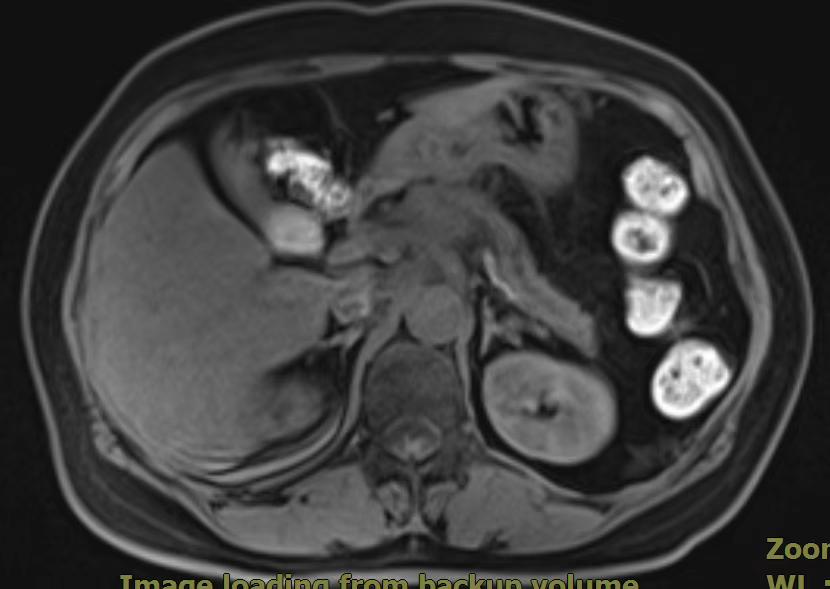

”鱼跃于源“之胰腺占位不明确?超声穿刺来诊断!癌中之王只能作以代毙?重离子带来新希望?

患者,女,60岁,主因“间断后背部胀痛1月。”2022-02-21就诊中国人民解放军中部战区总医院行腹部CT示:胰腺颈体部占位性病变并胰腺体尾部萎缩、胰管扩张,局部增大淋巴结,考虑胰腺癌可能;CA199 >1000U/ml;腹部核磁示:胰颈部占位性病变,考虑恶性肿瘤,胰腺Ca可能大,腹腔干、脾动脉、肝总动脉局部包绕其中,与门静脉边界欠清,胰体尾部萎缩、胰管扩张;胰头周围数枚淋巴结显示,部分增大,考虑转移。为进一步明确诊断,我院消化内三科为患者行超声胃镜检查及穿刺示:于胰颈部可见一2.5×3.0cm大小不规则低回声占位,肠系膜上静脉穿入其中,弹性成像提示:病变部分 略偏硬。胰腺体尾部胰管扩张,最宽处约3mm。超声穿刺病检结果示:(胰体占位穿刺组织)腺癌。在明确诊断前提下,碳离子治疗+化疗治疗;让“癌中之王”不再坐以待毙。